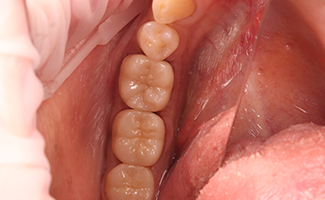

BEFORE

AFTER

ジルコニアとは、人工ダイヤモンドといわれる耐久性に優れた体に優しいセラミックです。スペースシャトルの外壁に使用されたり、医科では骨の代替材料として人工関節に使われるなど生体親和性に優れた、大変丈夫で安全な材料です。

現在、歯科の分野では、金属アレルギーの問題などからセラミックによる治療が注目されています。ジルコニアは、耐久性、耐食性、耐熱性に優れ、美しく、生体親和性も高いことから、金属に代わるものとして最も注目される材料です。